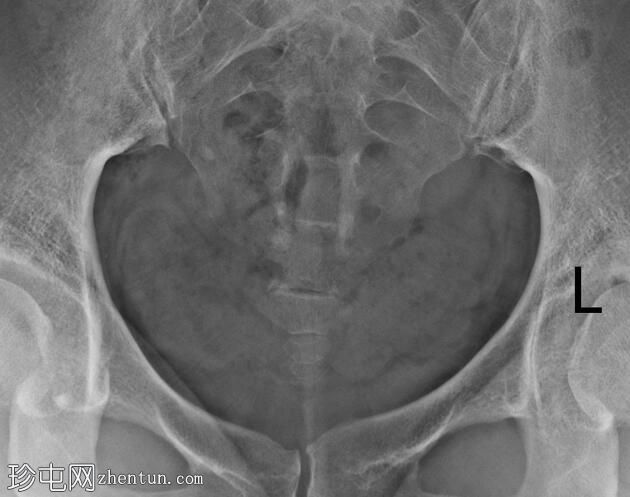

子宫体位于盆腔中线,形态及轮廓正常。

宫颈管长度正常,黏膜表面扩张良好。